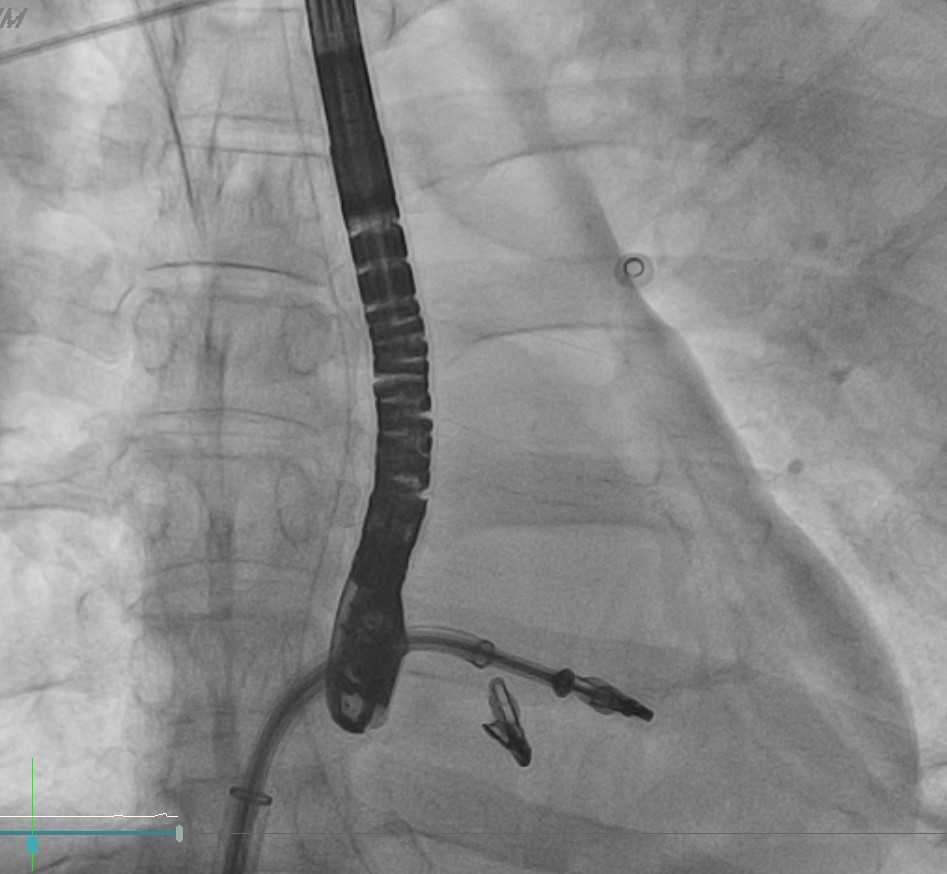

Coronary angiography revealed critical left main and triple-vessel coronary artery disease. The right coronary artery and posterolateral branch were totally occluded, serving as infarct-related lesions. TIMI flow improved from 0 to 3 after deployment of two drug-eluting stents in the RCA and RCA-PL. Residual severe disease in the left main, LAD, and LCX was reserved for staged PCI. Periprocedural VT was defibrillated twice (200 J) under VA-ECMO and IABP support.

Primary Intervention (Feb 28): During extracorporeal cardiopulmonary resuscitation, two drug-eluting stents were implanted in the right coronary artery and posterolateral branch under VA-ECMO and IABP support. Ventricular tachycardia during PCI was successfully defibrillated, and targeted temperature management was initiated.